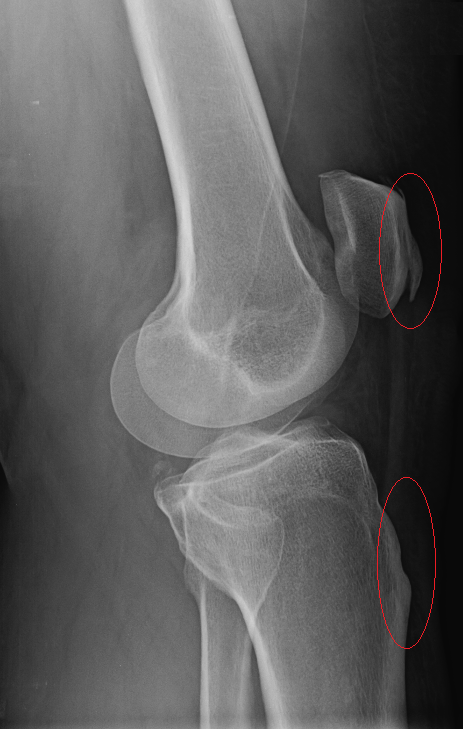

Your sunrise pateler views (bottom knee cap floating in space view) are worrying. You are developing bone avulsions (the part where it looks like it is separating) most likely due to impact injury coupled with straining tendons. You got to start wearing knee pads for what ever you are doing that is impacting them. If that continues in the same path, even walking will be a chore.

On the lateral view I can see see a section of calcification on the anterior aspect. ................... The worrying part is just bellow the calcium I see a region that looks like a chip fracture or an older one. Its the diagonal line with the offset. Of course, I could just be nitpicking and just seeing something that is an optical illusion.